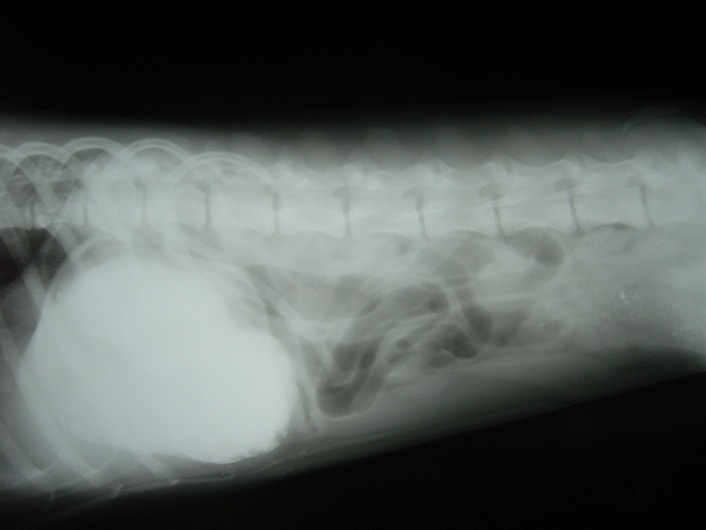

症例1:腸内異物

ボーダーコリー 9ヵ月 オス

主訴:食欲、元気はあるが食後2時間で未消化物を嘔吐。異物癖あり。

触診上、下腹部に5cm大の硬結物を確認。

◎各種検査結果

- ・血液検査:低カリウム血症

- ・レントゲン検査:胃ガス、腸内ガス陰影、空腸領域に不透過性の陰影あり。

- ・バリウム造影検査:造影後2時間、胃からのバリウム排泄なし。

- 上記検査結果より、同日、内視鏡検査ならびに腸内異物摘出術を実施。

- 内視鏡検査:胃内にて4cm大のロープ様の異物を摘出。胃内、十二指腸内に炎症像が認められた。

◎腸内異物摘出術

本症例は、 おもちゃのロープを誤飲したことにより腸で通過障害を引き起こし、嘔吐として症状が認められた。現在のところ、一般状態に問題なく経過観察を指示。